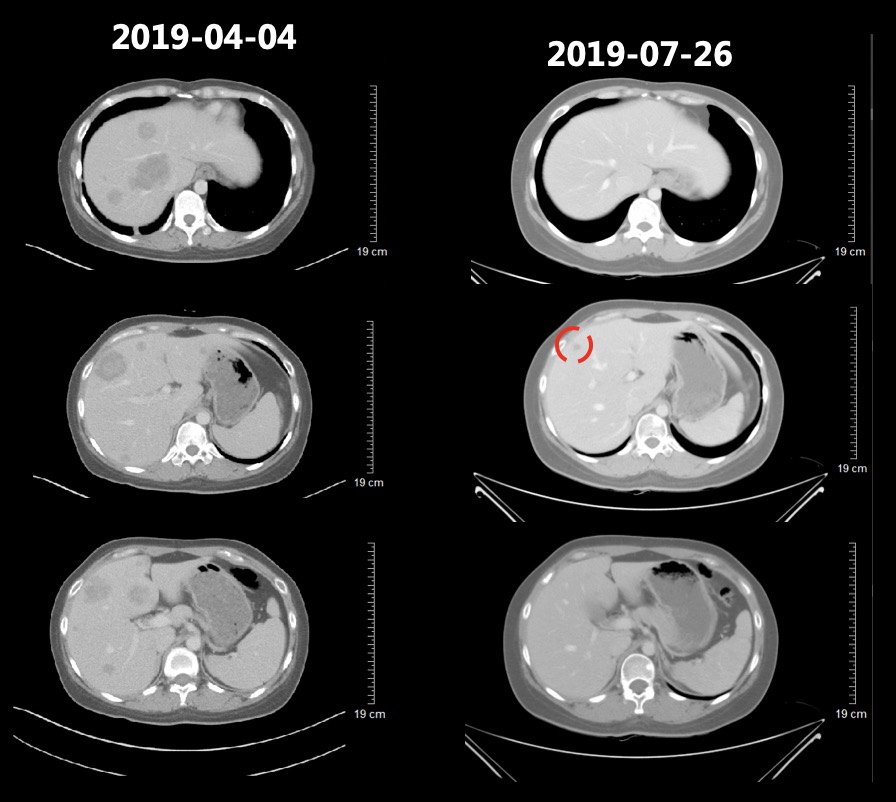

患者于2019-06-12、07-08继续行第4-5周期三线方案(信迪利单抗+白蛋白紫杉醇 ,每三周一次),2019-07-26复查胸腹部CT提示,肺部病灶较前明显缩小,肝脏病灶较前明显缩小。T2、T9-L2椎体及L2左侧附件多发骨转移同前(图7)。患者肿瘤标志物也基本呈现下降趋势(图8),疗效评价为(PR)。

图7 2019-07-26复查胸腹部CT提示,肺部病灶较前明显缩小,肝脏病灶较前明显缩小。T2、T9-L2椎体及L2左侧附件多发骨转移同前